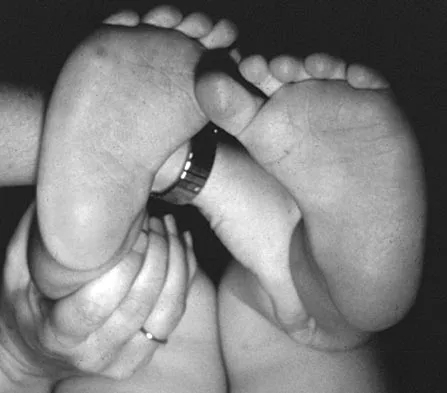

Figure 16 shows the clinical photograph of a 3-month-old infant with a foot deformity that has been nonprogressive since birth. Examination reveals that the deformity corrects actively and with passive manipulation. There is no associated equinus. Management should consist of

Explanation

An 18-month-old infant with myelomeningocele and rigid clubfeet has grade 5 quadriceps and hamstring strength, but no muscles are functioning below the knee. What is the best treatment option for the rigid clubfeet?

Explanation

A newborn with bilateral talipes equinovarus undergoes serial manipulation and casting. What is the primary goal of manipulation?

Explanation